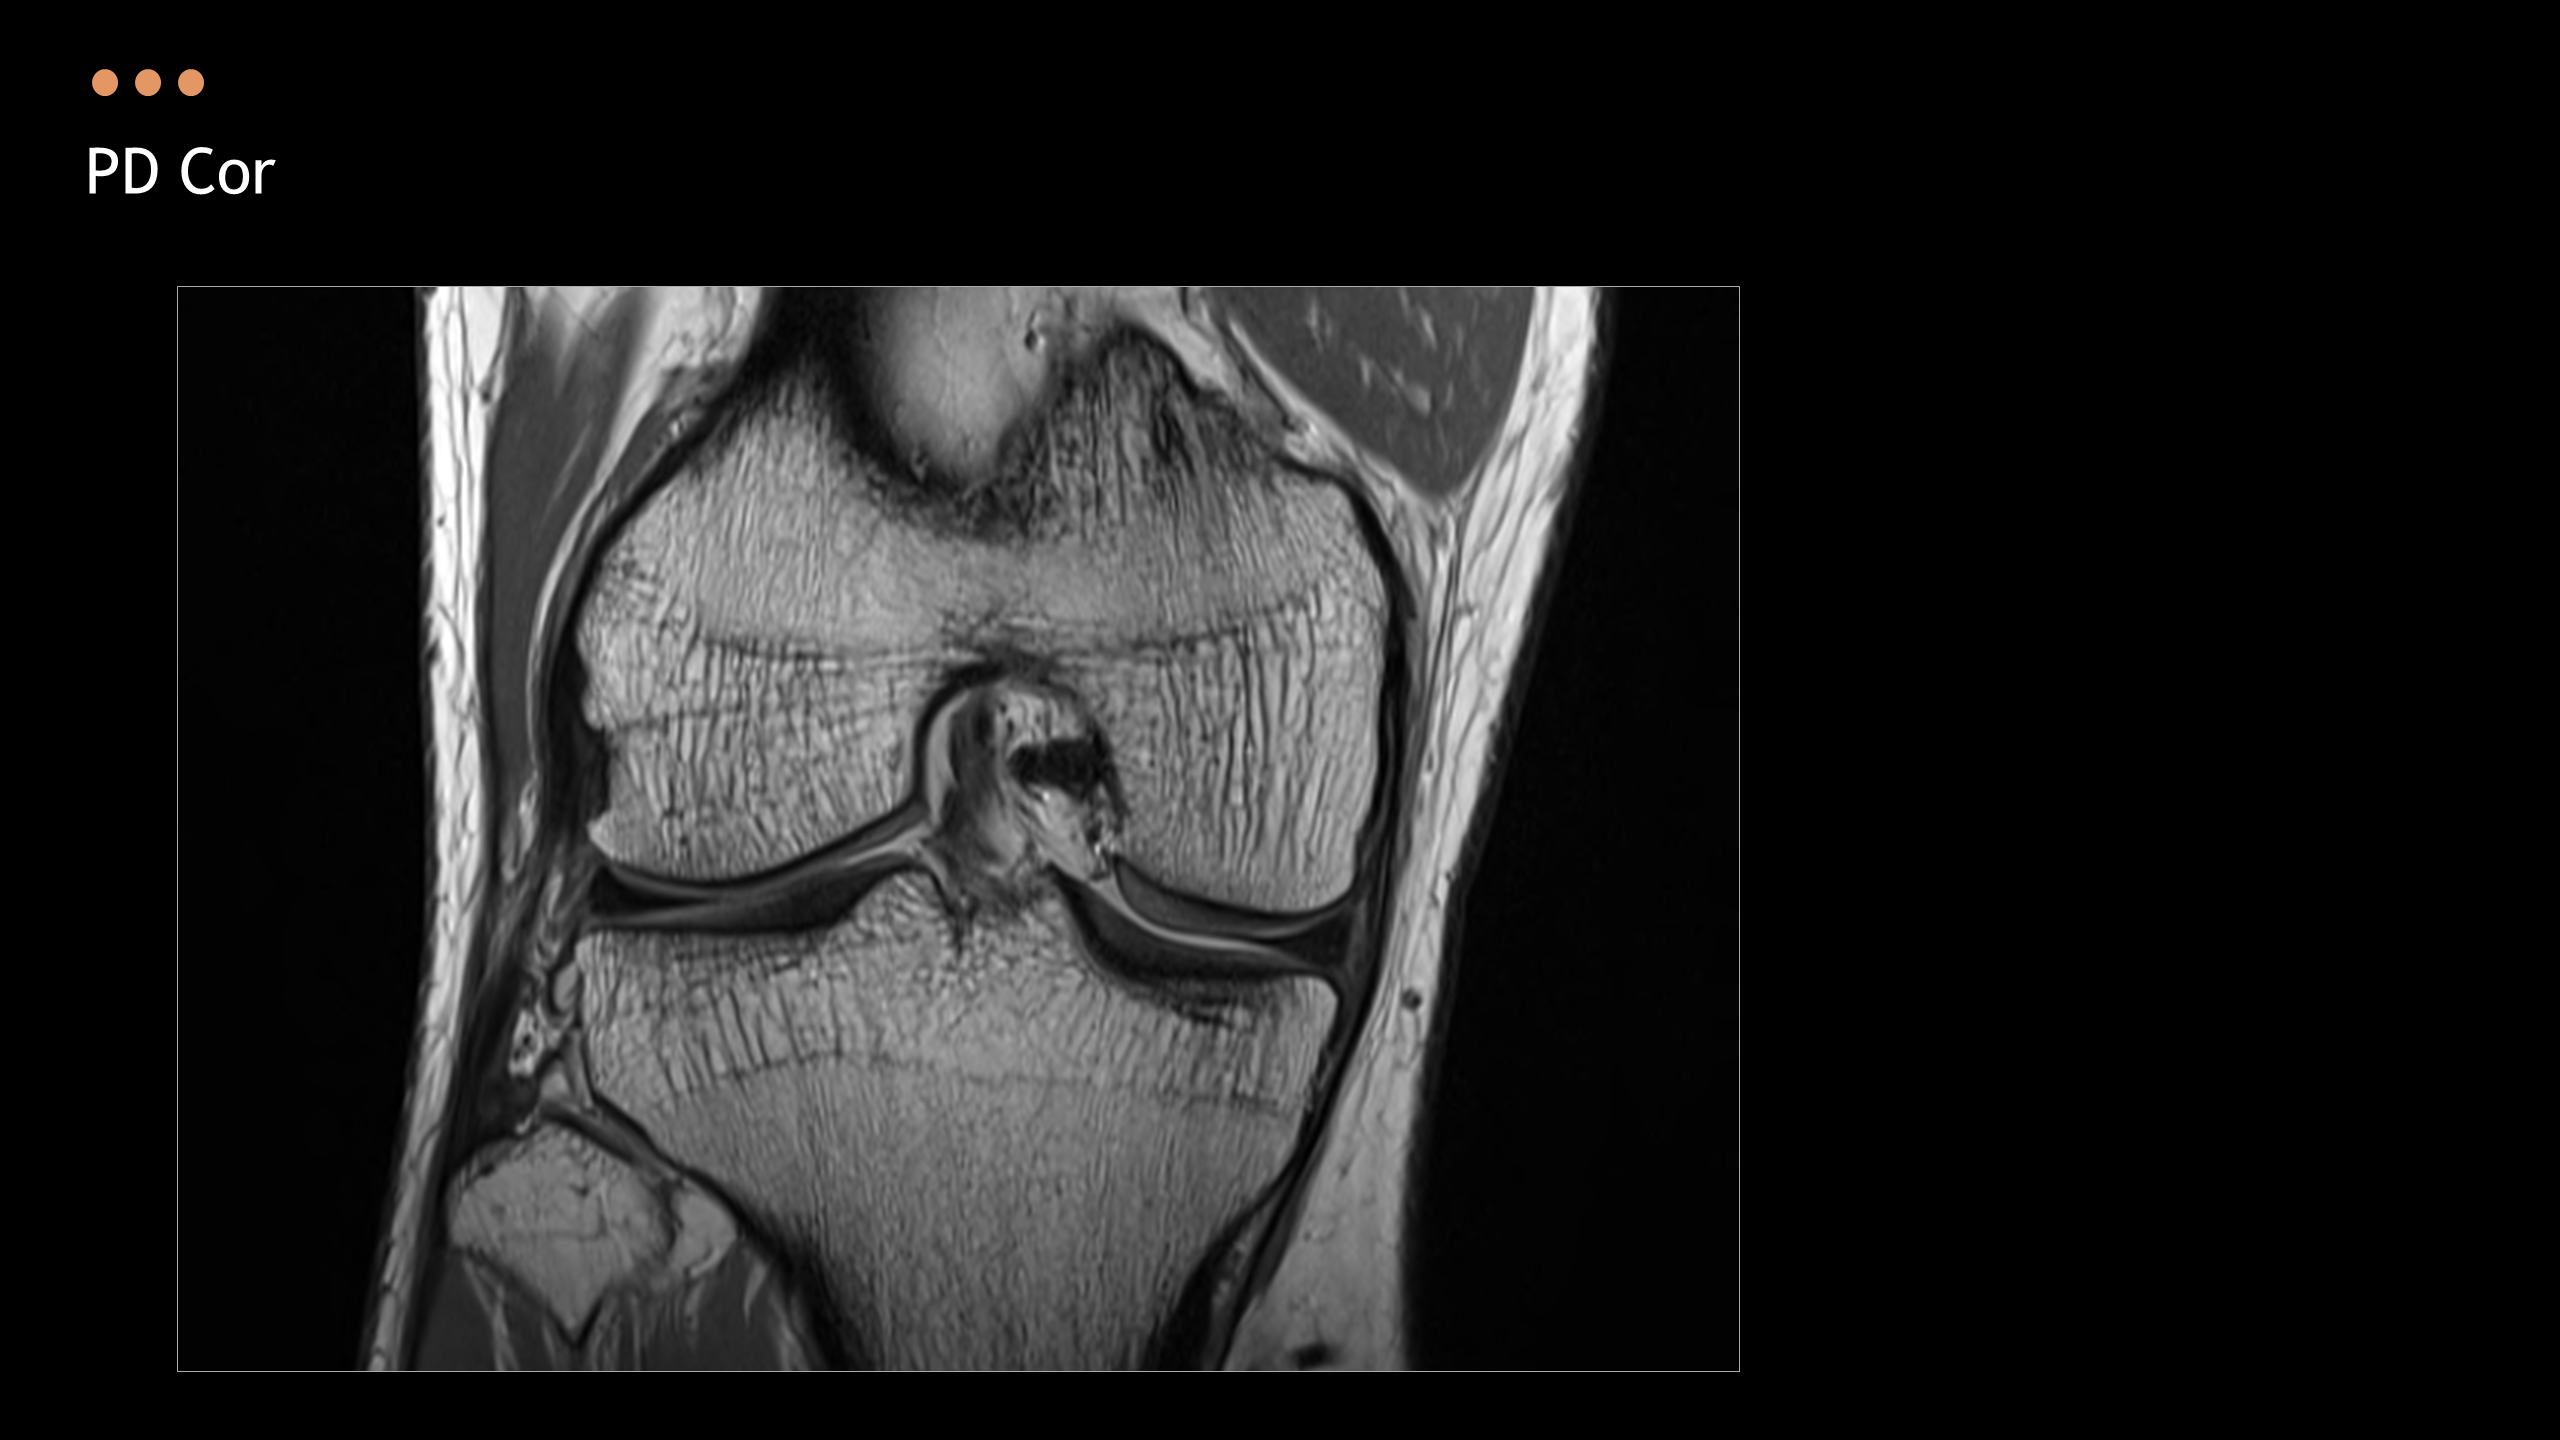

주제: The Knee MRI Approach

강사: 신민섭

아래의 Normal Knee MR Anatomy를 숙지하고 오셔야, 강의에 어려움이 없습니다.